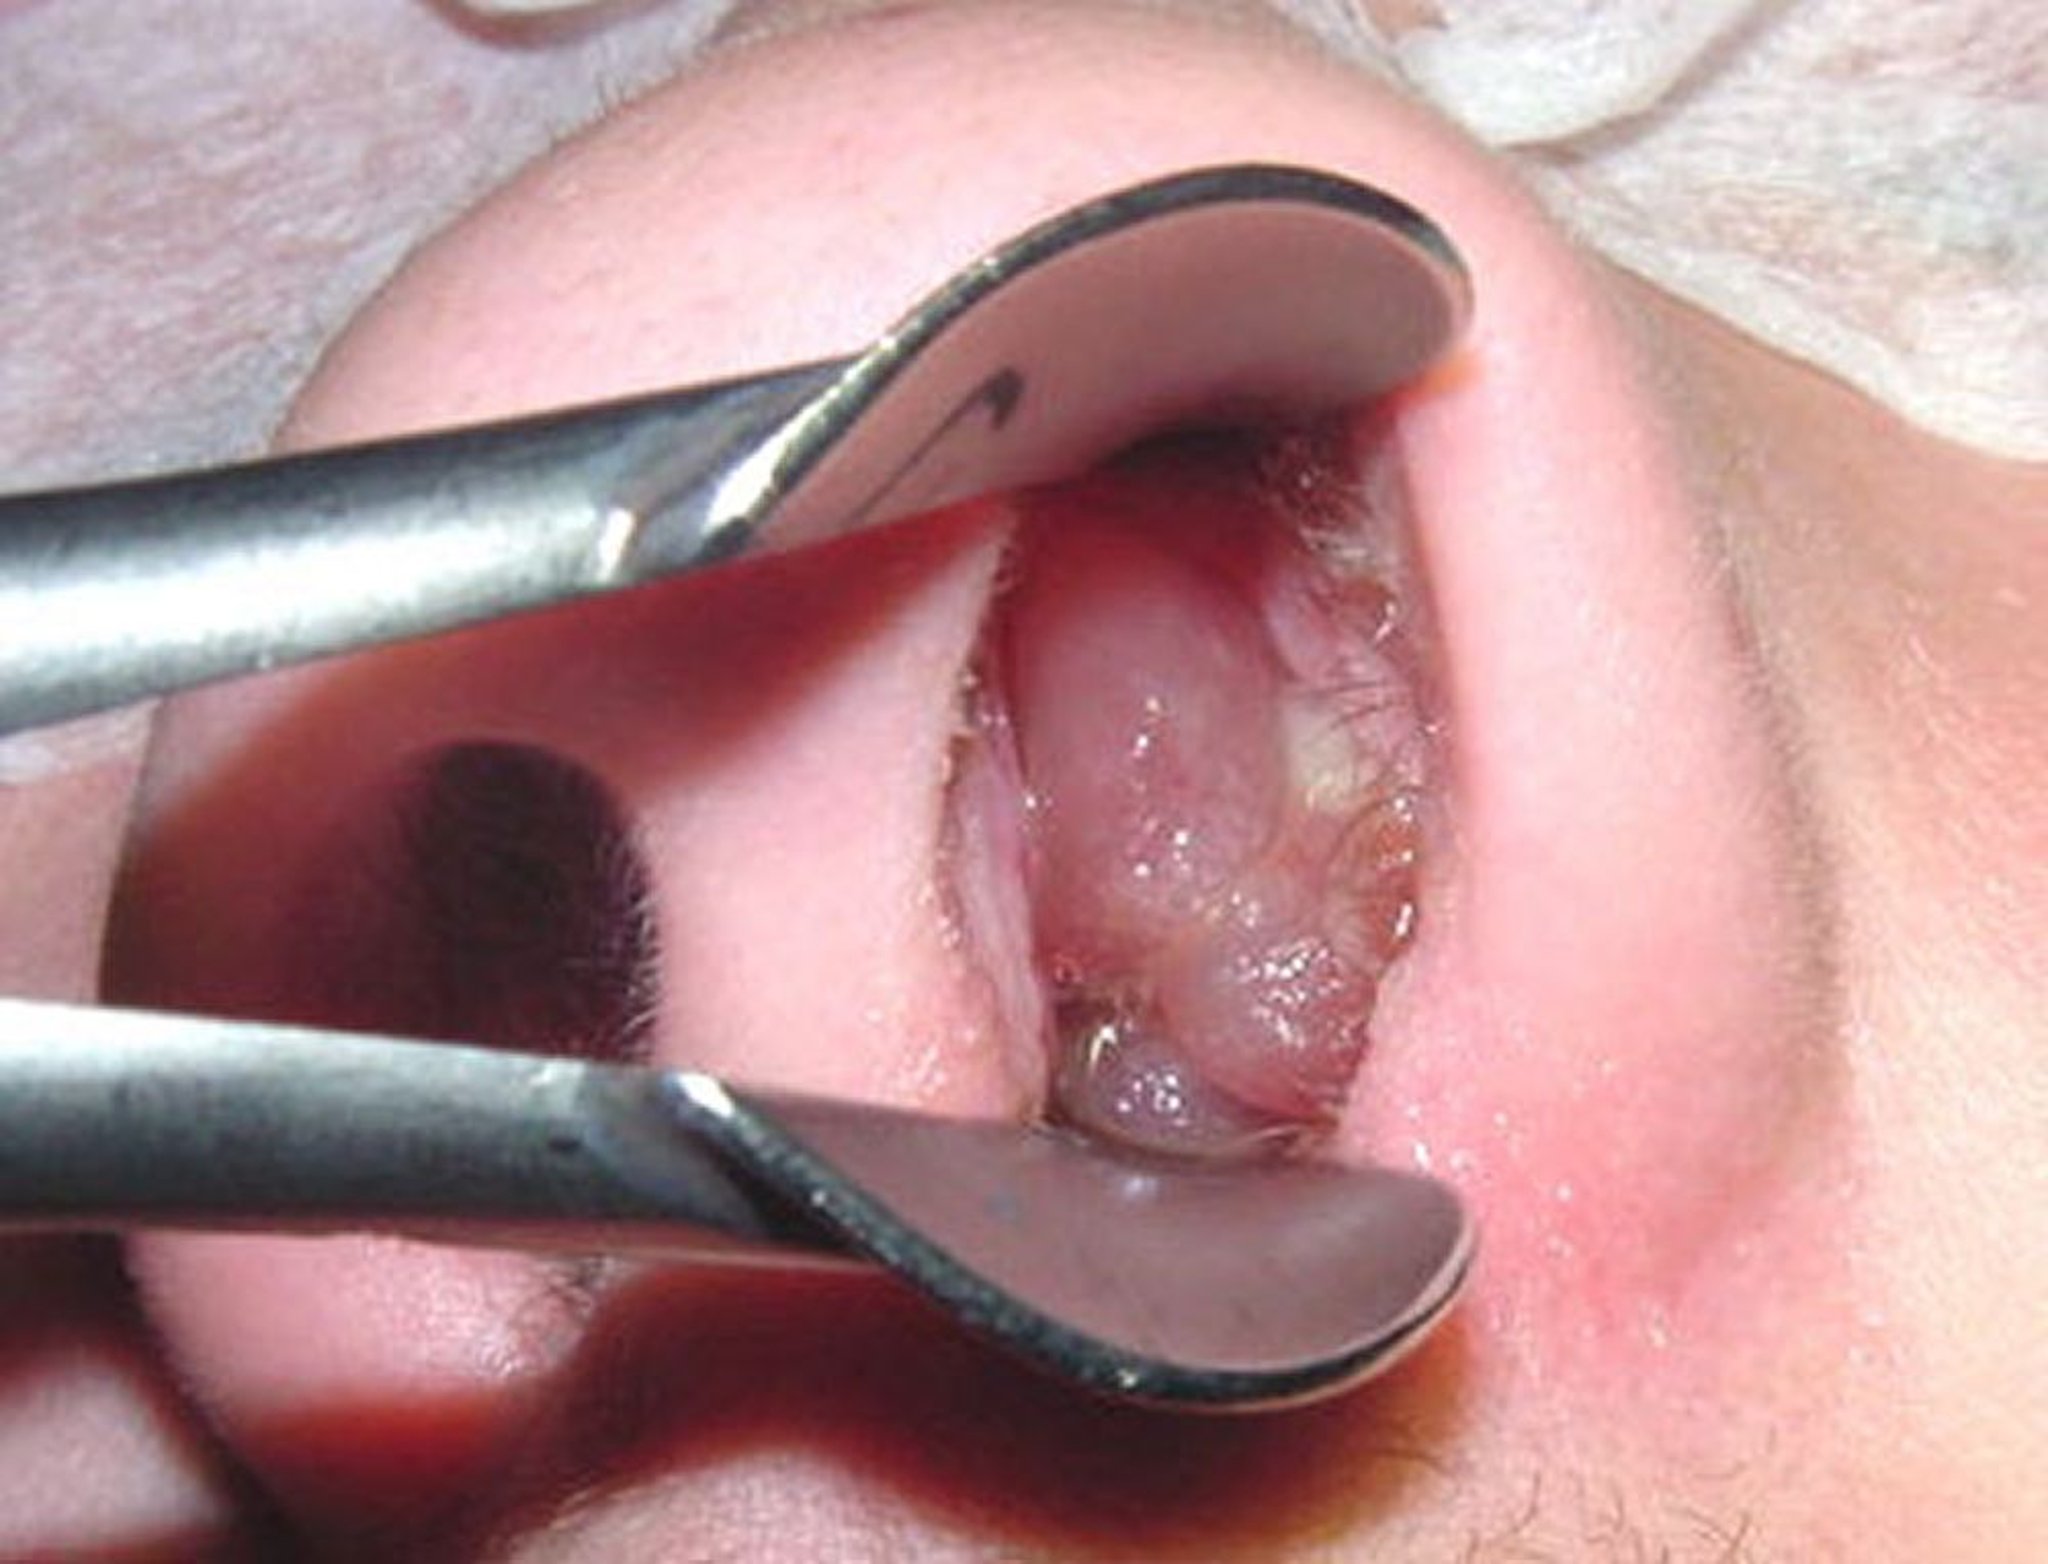

鼻茸

成熟した鼻茸は,皮をむいた種なしブドウに似ていることがある。

Image provided by Bechara Ghorayeb, MD.